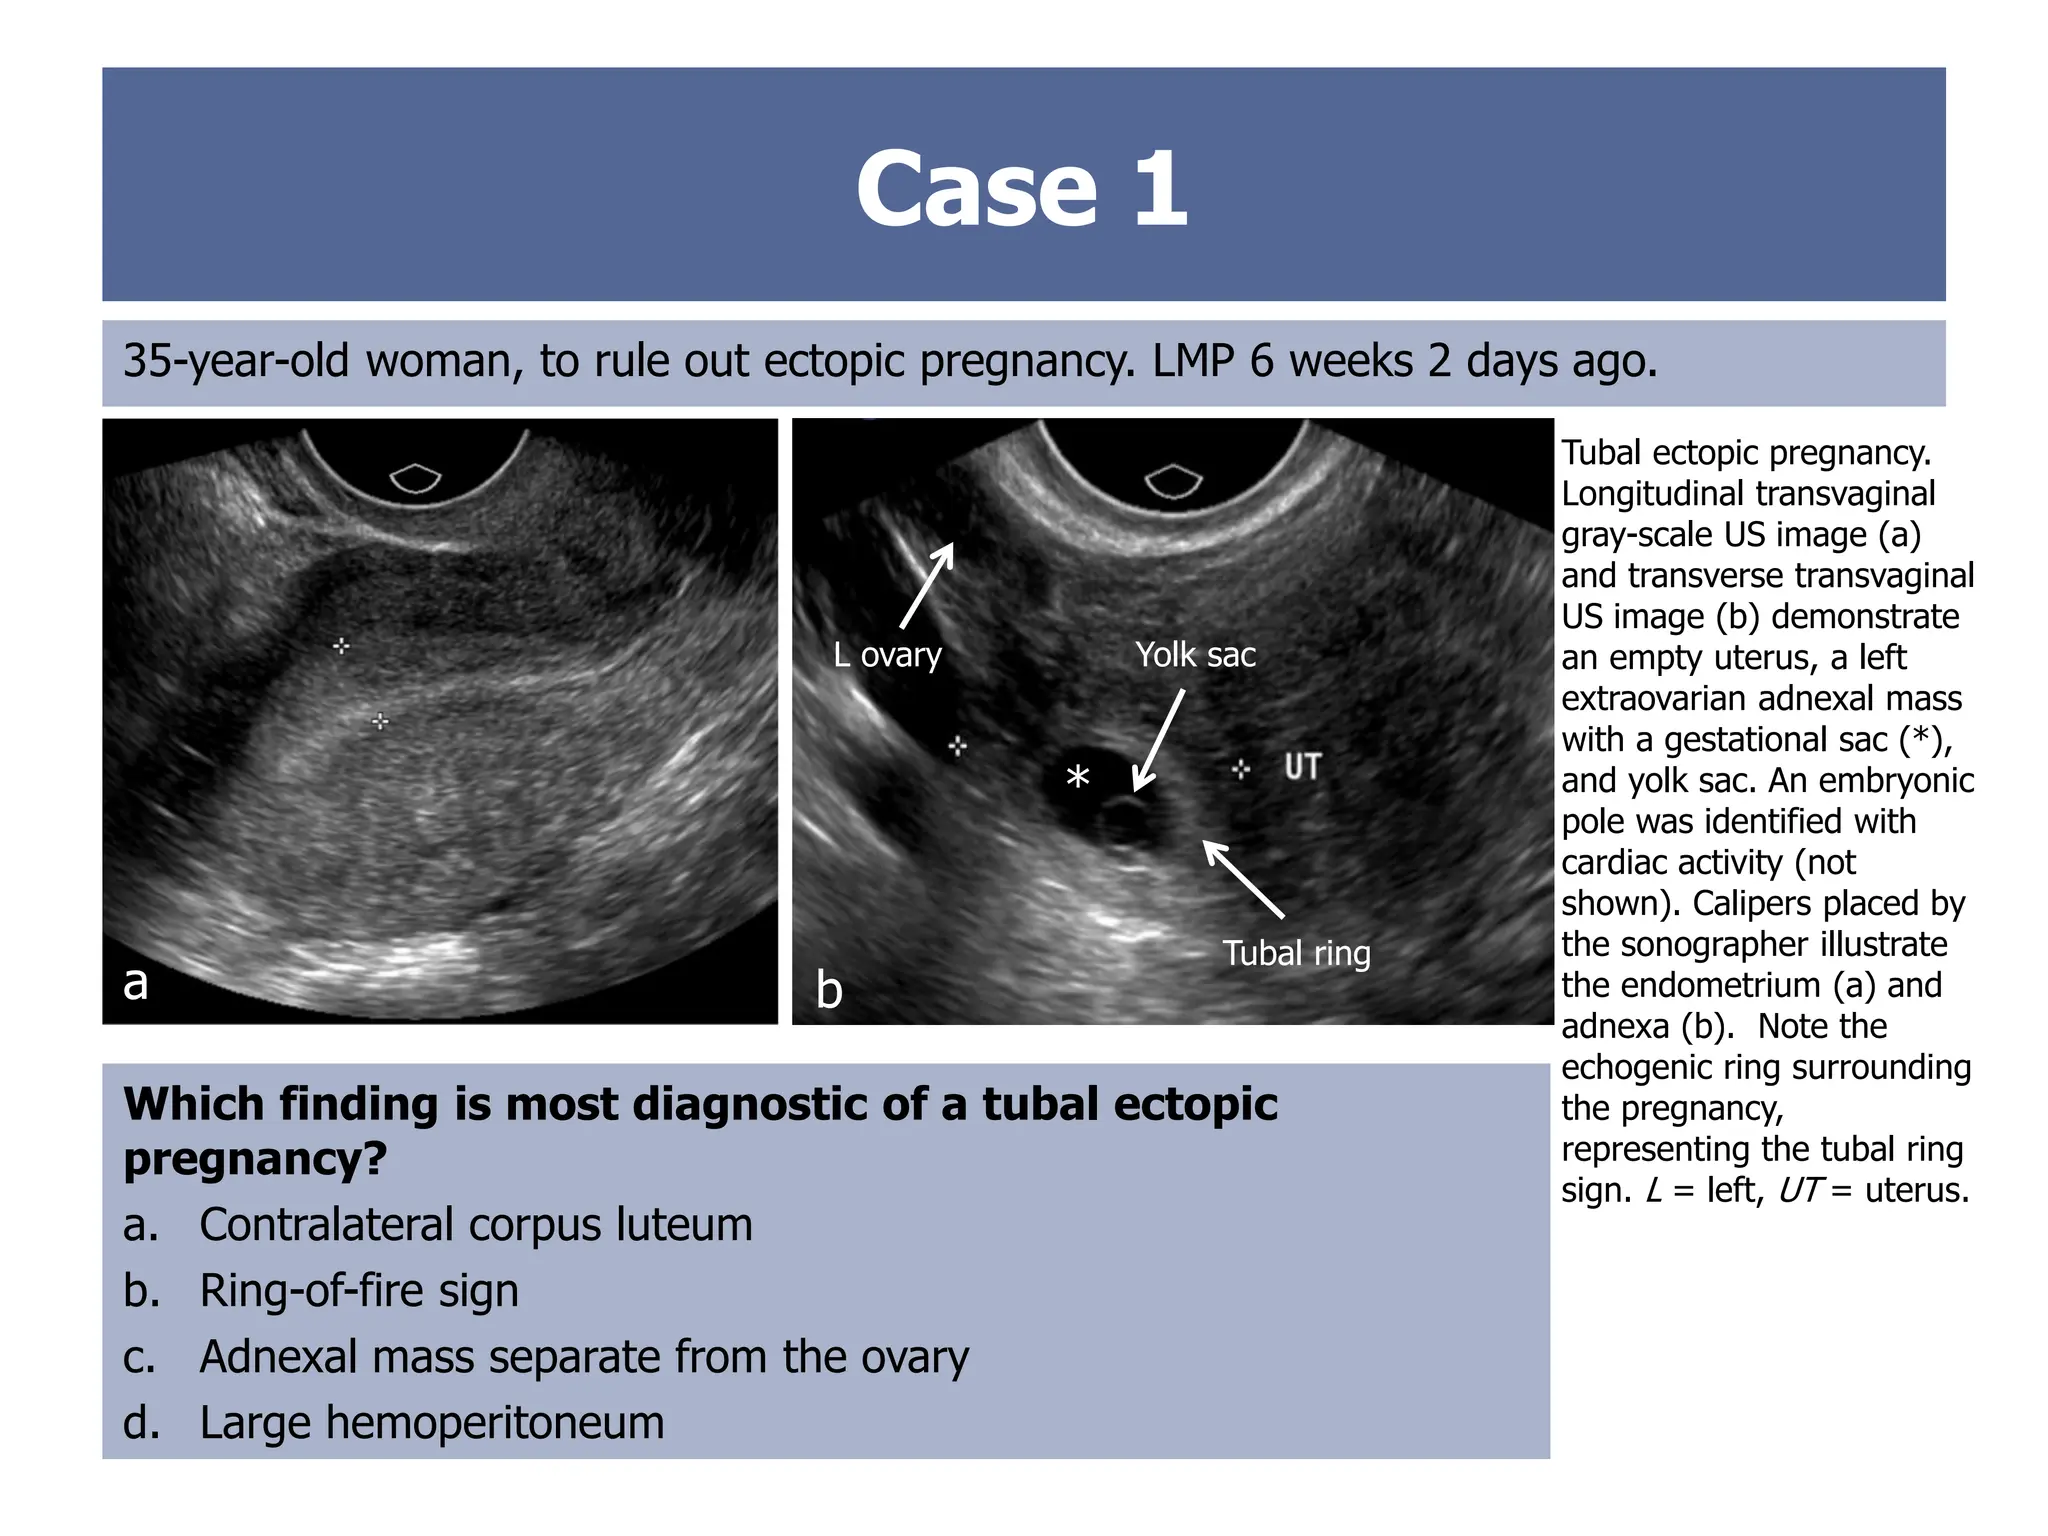

35-year-old woman, to rule out ectopic pregnancy. LMP 6 weeks 2 days ago.

Tubal ectopic pregnancy.

Longitudinal transvaginal

gray-scale US image (a)

and transverse transvaginal

US image (b) demonstrate

an empty uterus, a left

extraovarian adnexal mass

with a gestational sac (*),

and yolk sac. An embryonic

pole was identified with

cardiac activity (not

shown). Calipers placed by

the sonographer illustrate

the endometrium (a) and

adnexa (b). Note the

echogenic ring surrounding

the pregnancy,

representing the tubal ring

sign. L = left, UT = uterus.

Which finding is most diagnostic of a tubal ectopic

pregnancy?

a. Contralateral corpus luteum

b. Ring-of-fire sign

c. Adnexal mass separate from the ovary

d. Large hemoperitoneum